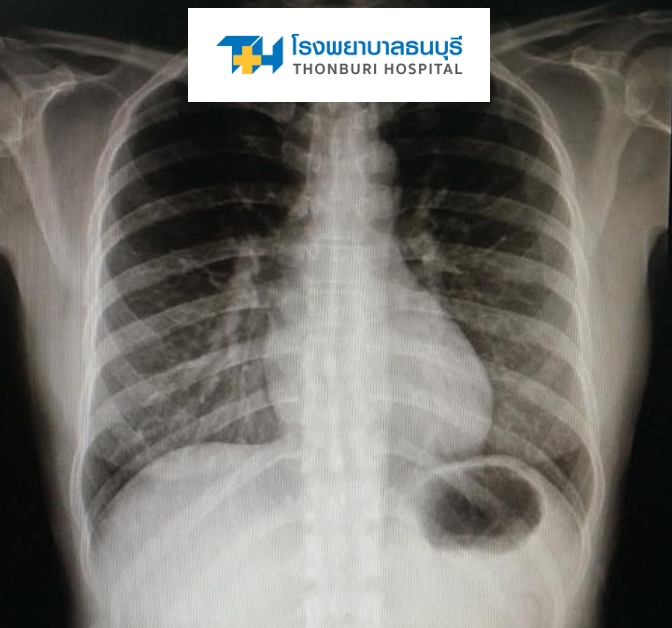

♦ นำฟิล์มเอกซเรย์ปอดมาด้วยถ้ามี